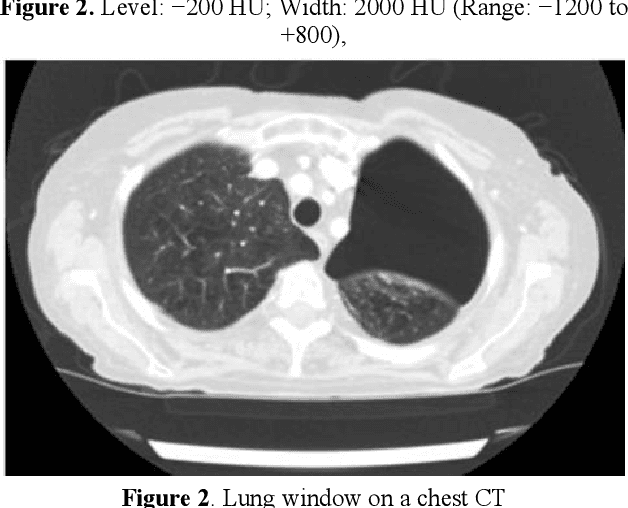

Abstract:At present, the incidence and fatality rate of lung cancer in China rank first among all malignant tumors. Despite the continuous development and improvement of China's medical level, the overall 5-year survival rate of lung cancer patients is still lower than 20% and is staged. A number of studies have confirmed that early diagnosis and treatment of early stage lung cancer is of great significance to improve the prognosis of patients. In recent years, artificial intelligence technology has gradually begun to be applied in oncology. ai is used in cancer screening, clinical diagnosis, radiation therapy (image acquisition, at-risk organ segmentation, image calibration and delivery) and other aspects of rapid development. However, whether medical ai can be socialized depends on the public's attitude and acceptance to a certain extent. However, at present, there are few studies on the diagnosis of early lung cancer by AI technology combined with SCT scanning. In view of this, this study applied the combined method in early lung cancer screening, aiming to find a safe and efficient screening mode and provide a reference for clinical diagnosis and treatment.